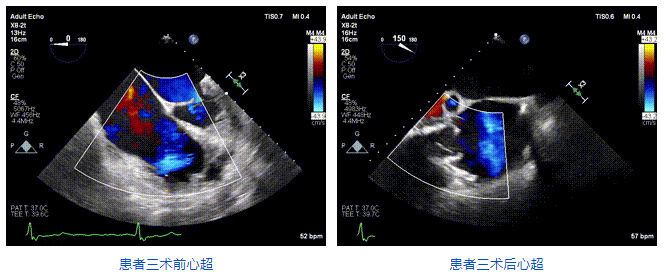

2021年12月24日,復(fù)旦大學(xué)附屬中山醫(yī)院葛均波院士團(tuán)隊(duì)成功應(yīng)用LuX-Valve Plus為一例極重度三尖瓣反流(TR)合并房顫、房缺的患者完成了經(jīng)血管三尖瓣置換術(shù),這是在前基礎(chǔ)上,本周完成的第三例經(jīng)血管三尖瓣置換手術(shù),葛均波院士、周達(dá)新教授等與心外科魏來教授、賴顥教授,心超室的潘翠珍教授、李偉教授及麻醉科的郭克芳教授共同完成了本周手術(shù),均獲得圓滿成功!患者術(shù)后超聲顯示無TR,臨床癥狀明顯改善。本周手術(shù)的成功也為LuX-Valve Plus救治性臨床研究添上了濃墨重彩的一筆。

三例患者入院后,葛均波院士團(tuán)隊(duì)周達(dá)新教授、潘文志教授、張?jiān)床┦?、陳莎莎博士及心超室的潘翠珍教授、李偉教授對患者的情況進(jìn)行詳細(xì)評估和討論,最終決定為三例患者選擇LuX-Valve Plus40mm、50mm和50mm型號的瓣膜進(jìn)行手術(shù)治療。手術(shù)后即刻拔除氣管插管,術(shù)后患者三尖瓣反流癥狀得到顯著改善,復(fù)查心超結(jié)果顯示人工三尖瓣瓣膜支架固定穩(wěn)定,瓣葉關(guān)閉形態(tài)未見異常,未見明顯反流。